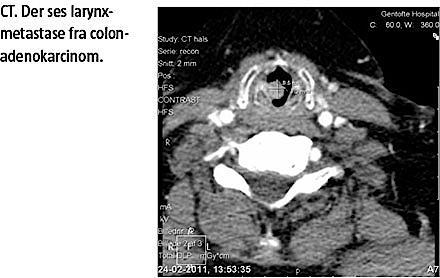

punktet. Hun havde gennem 14 dage haft tiltagende kriller i halsen og let besværet vejrtrækning. Der var intet utilsigtet vægttab og ingen halssmerter. Objektivt fandt man, at stemmen var diskret forandret. Der var ingen stridor. En fiberlaryngoskopi viste en pendulerende benignt udseende tumor, hvor slimhinden var glat og ikke ulcerende eller polypøs og inddrog 70-80% af tracheas lumen. Tumoren udgik fra underkanten af højre plica vocalis. En CT af hals, thorax og øvre abdomen viste en tumor på 50 × 8 × 7 mm. Tumoren strakte sig fra plica vocalis og ned til overkanten af TH1 (Figur 1). Der blev ved samme skanning fundet et infiltrat i venstre lunges underlap. Dette infiltrat var uændret fra tidligere skanninger og gav ikke mistanke om lungemetastase. Larynxmetastasen var således den eneste metastase fra coloncanceren og ikke en del af en dissemineret sygdom på operationstidspunktet. Tumoren blev fjernet makroskopisk radikalt ved et mikrolaryngoskopisk indgreb. Den efterfølgende histologiske undersøgelse viste, at der var metastase fra et adenokarcinom med primær udgangspunkt i patientens tidligere colonadenokarcinom. Tumoren var kraftig positiv for CDX2 og dispers positiv i CK20 og negativ CK7. Patienten blev henvist til en onkologisk afdeling til videre opfølgning og fik efterfølgende strålebehandling på et lille larynxfelt, da man ikke kunne se, om der var frie resektionsrande. Ved en efterfølgende kontrol blev der ikke fundet recidiv i larynx, men derimod metastaser til lungerne og colon sigmoideum. Patienten var fortsat i live efter seks måneder.